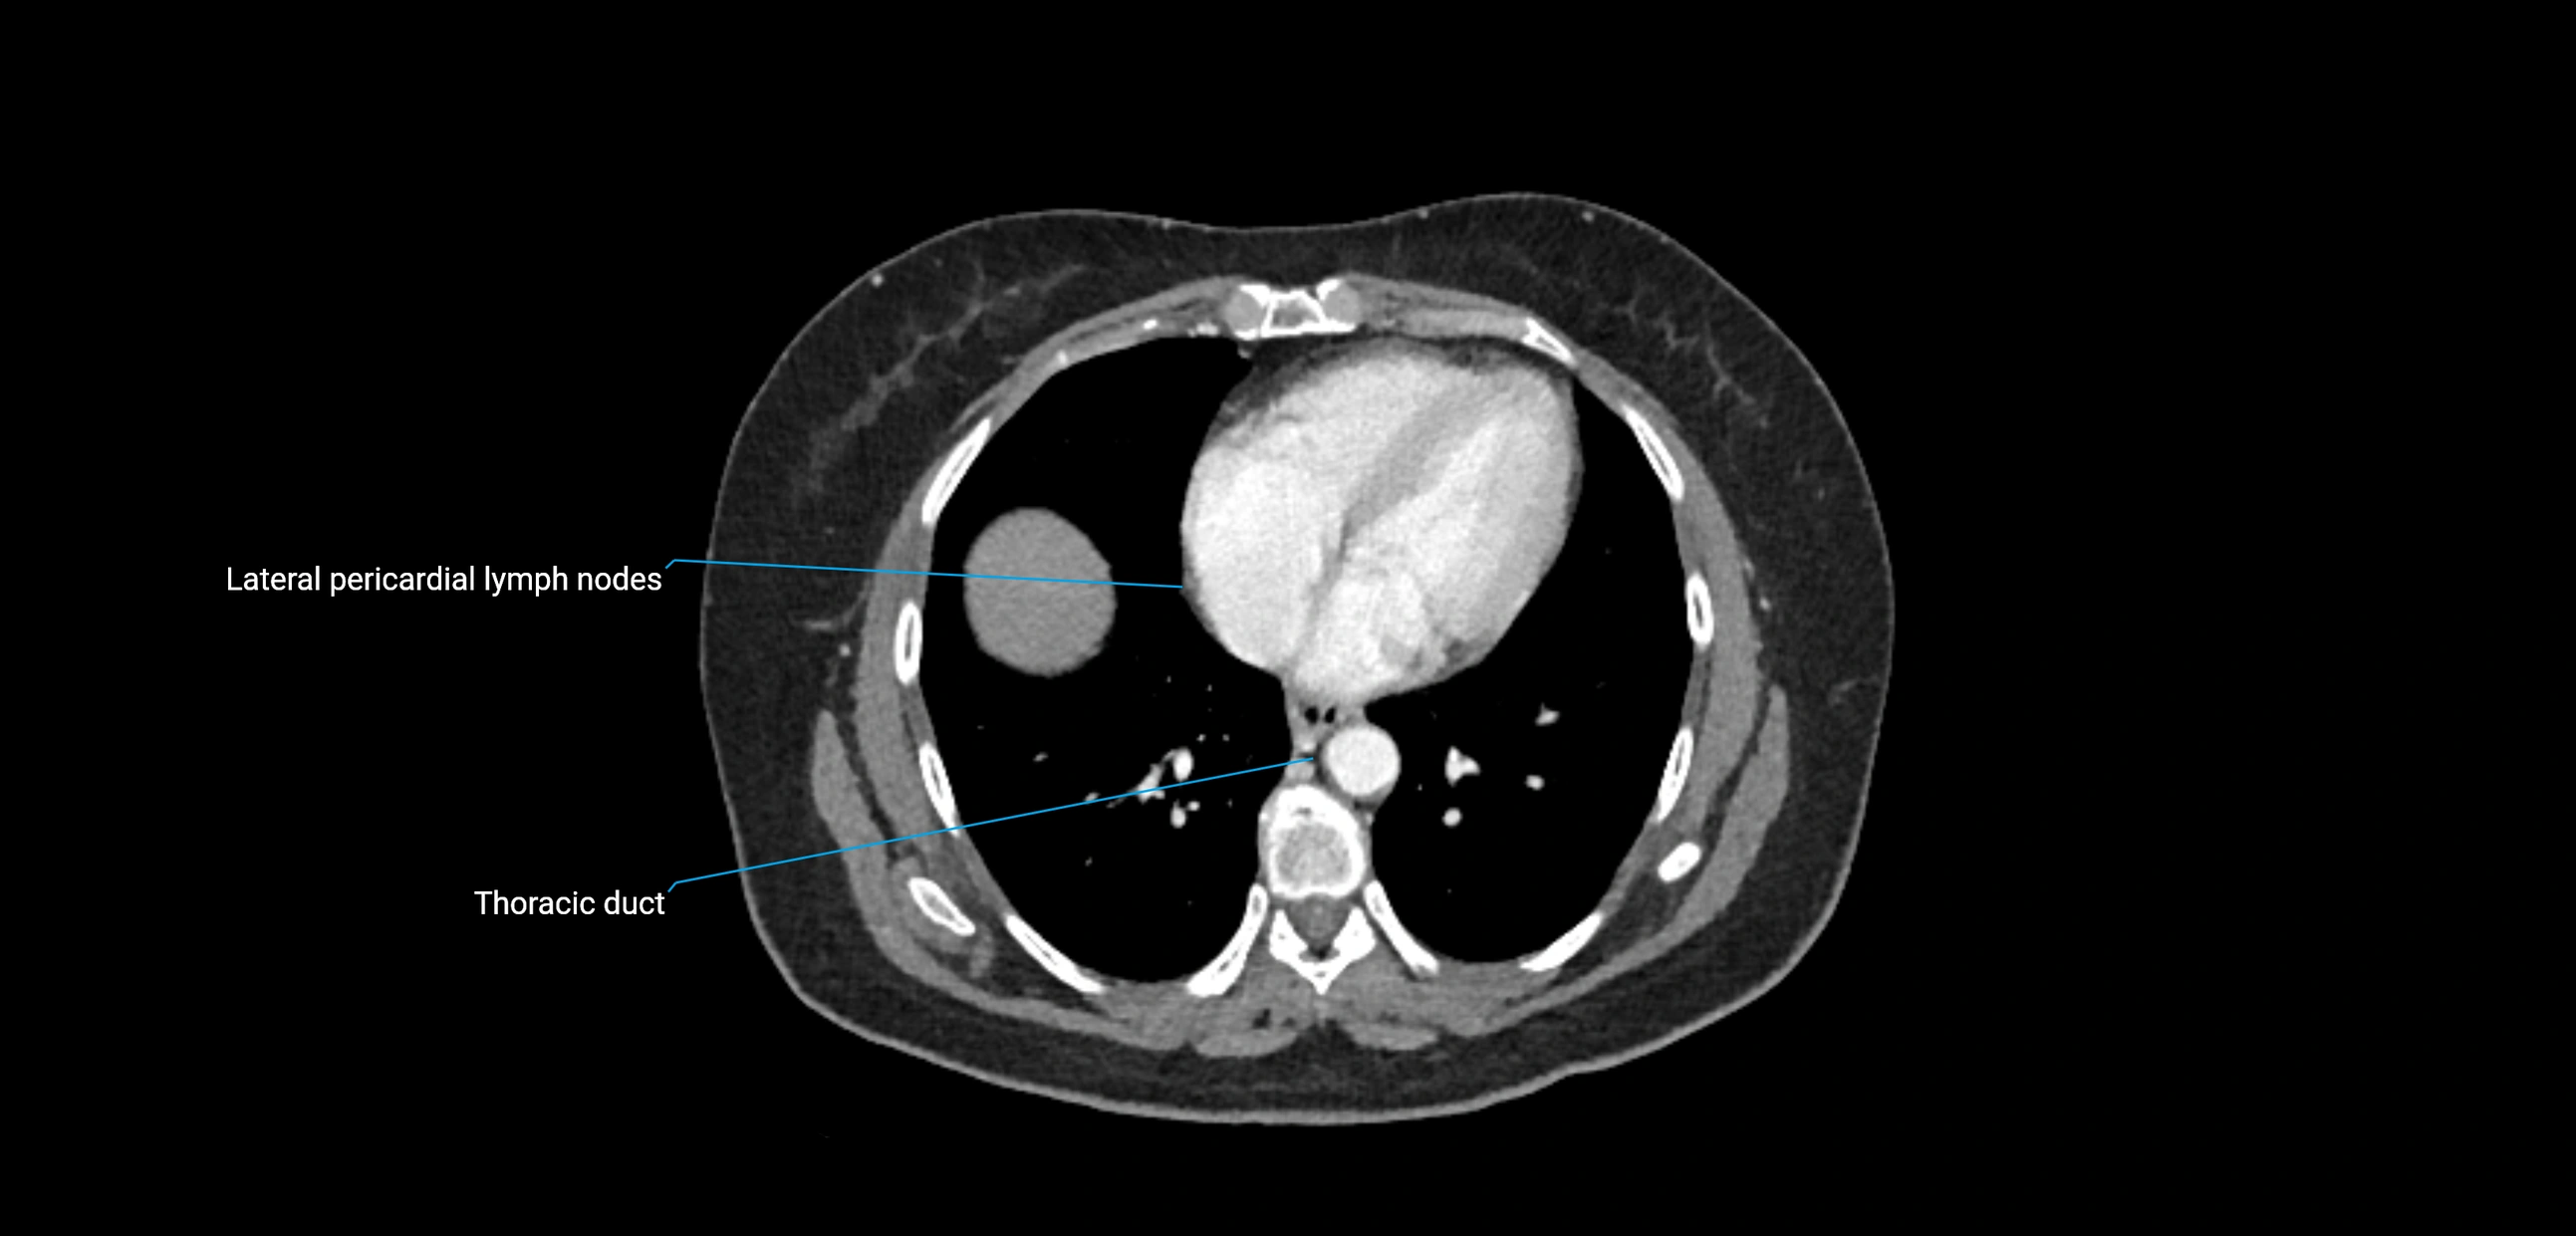

These nodes receive lymph from a wide range of abdominal and pelvic structures. Specifically, they drain lymph from the kidneys, suprarenal glands, gonads (testes/ovaries), uterus, uterine tubes, and pelvic organs, before converging into the lumbar lymphatic trunks, which terminate in the cisterna chyli → thoracic duct.

• Provide a major pathway to the cisterna chyli and thoracic duct